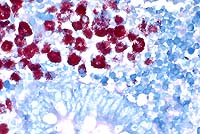

The macrophages throughout the intestinal lesions are distended

with mycobacteria, confirmed by Ziehl Nielsen stains, but apparent

as fine basophilic cytoplasmic stippling in H&E-stained sections.

Conference Note: Some sections viewed in conference contain small numbers of coccidia with morphology consistent with Eimeria spp.

The intestinal macrophage is the target cell for infection by M. a. paratuberculosis. After the organisms are ingested, they undergo endocytosis by intestinal M cells. Intact and degraded mycobacteria are transported in vacuoles across the M cells to macrophages in subepithelial areas. Specific macrophage receptors for this organism have not been identified, although other mycobacteria use complement receptor types 1 and 3 on macrophages. After uptake by macrophages, the bacteria often resist the degradative and killing mechanisms of the macrophage via sulphatide production, which prevents phagosome-lysosome fusion, escape from the phagosome into the cytoplasm, glycolipid-mediated inhibition of nitric oxide production, and inhibition of the respiratory burst and oxidative killing mechanisms by superoxide dismutase and glycolipid production.